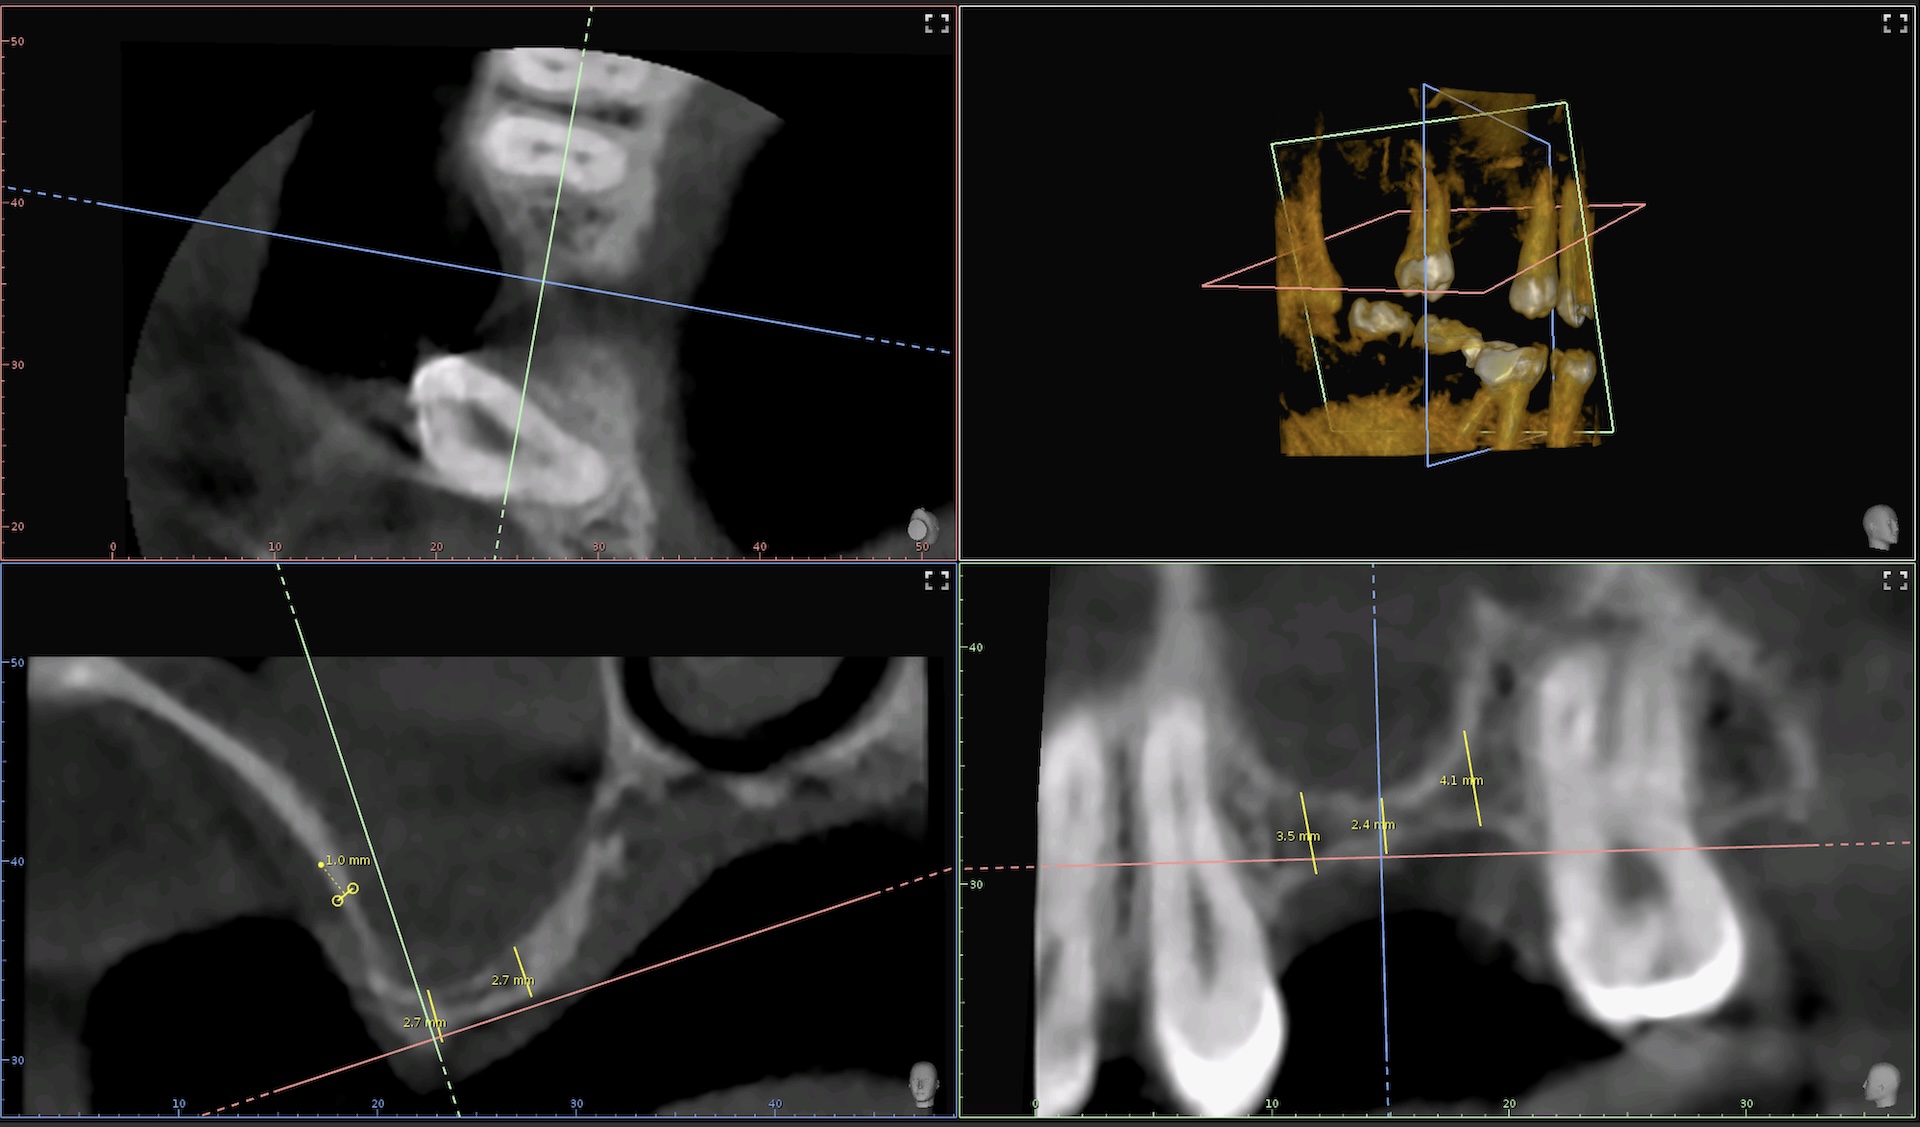

Alle zwei bis drei Jahre sollte eine röntgenologische Kariesfrüherkennungsuntersuchung durchgeführt werden. um Karies auch an versteckten Stellen, zum Beispiel in Zahnzwischenräumen und an unter dem Zahnfleisch liegenden Stellen rechtzeitig erkennen zu können. Durch die 3D Aufnahmetechnik können wir für die Implantologie und für die Endodontologie dreidimensionale Strukturen von Zähnen und Knochen darstellen.

Falls ein Zahn trotz aller Bemühungen nicht erhalten werden kann, bieten sich Implantate als Substanz schon in der Ersatz an. Ein Implantat ist eine künstliche Zahnwurzel, die im Kieferknochen verankert wird. Darauf lässt sich eine Krone befestigen, mit der man wie auf einem natürlichen Zahn kauen kann. Somit kann das Abschleifen von gesunden Zähnen, z. B. für eine Brücke vermieden werden. Durch den Einsatz von dreidimensional Röntgen (DVT) wird eine besonders präzise Implantatsetzung ermöglicht. Man Kann vor der OP den Knochen vermessen und die Lage der Implantate digital planen.